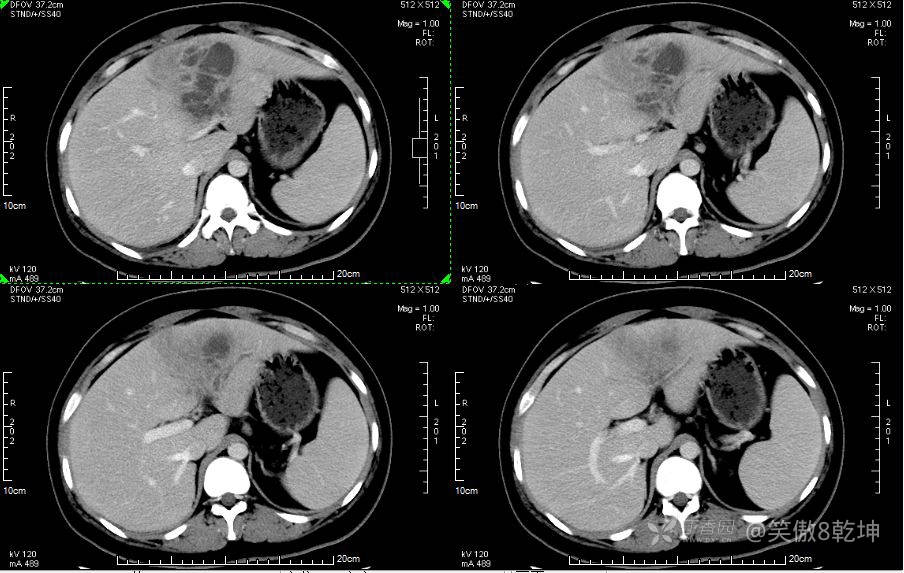

诊断似乎倾向于肝脓肿了,与患者或家属沟通后完善上腹部强化CT:

证实为肝脓肿,至此,诊断思路似乎清晰起来,患者血糖的升高使得微小血管容易出现循环障碍,同时白细胞的吞噬能力及抗感染能力下降,所有易出现感染性疾病。而肝脓肿通常不容易早期发现。患者的年龄同时让临床医生不容易想到此诊断。